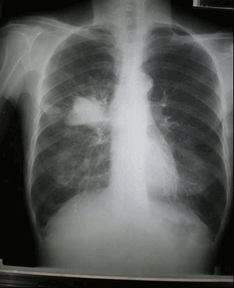

左肺下叶巨大软组织肿块 肺癌?

第三章 病例分析——肺癌

肺癌ct图片